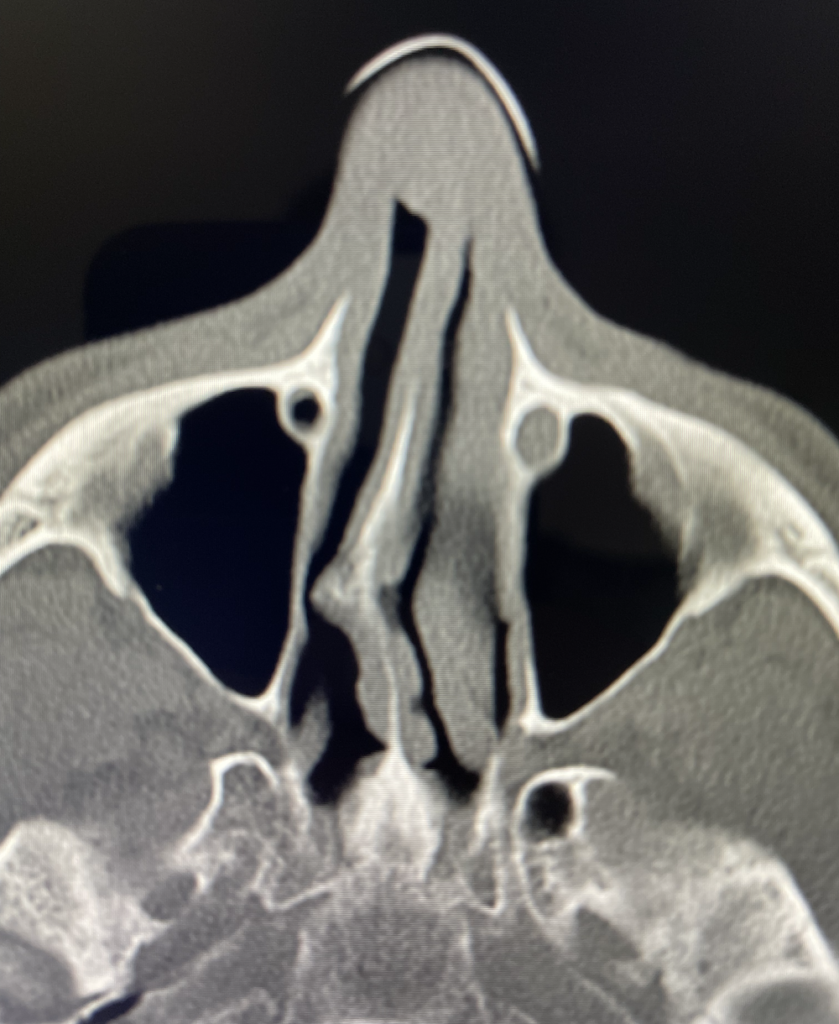

What you're looking at below is a CT scan of my head.

A septum should be fairly straight, making it possible for the nasal passage to work as intended. My deviated septum appears to have blocked passage, making it possible for the snap, crackle, pops to get worse and worse.